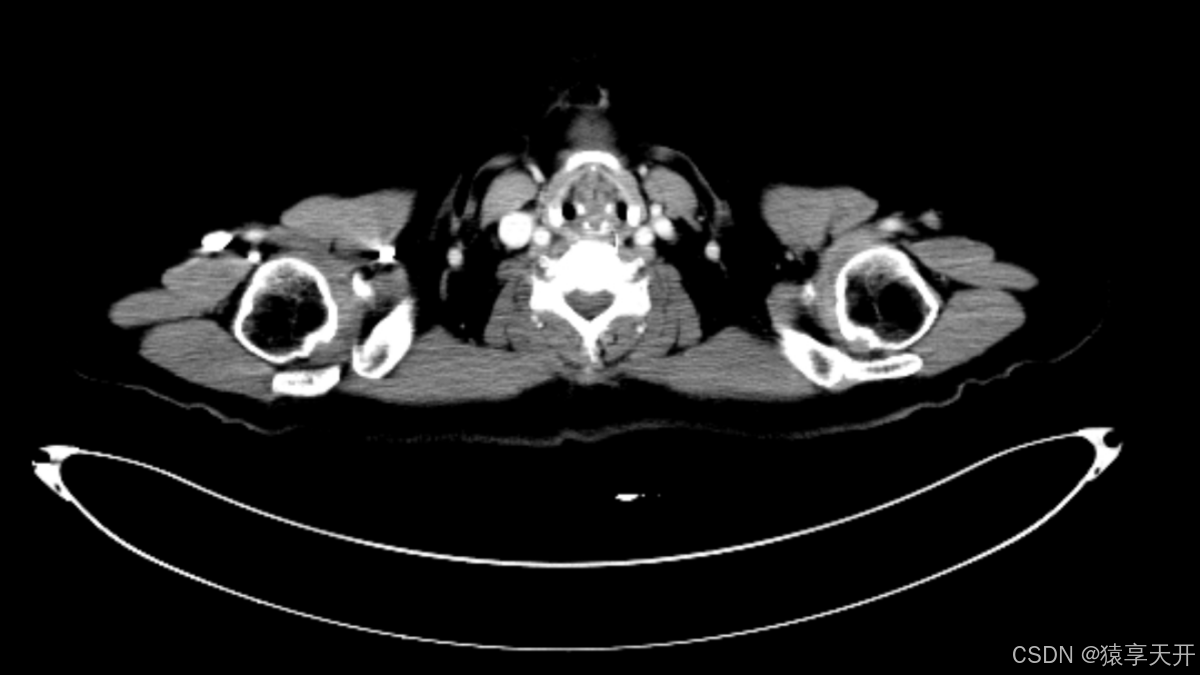

**视野(FOV, Field of View)**这个概念我们可能会有点陌生&#